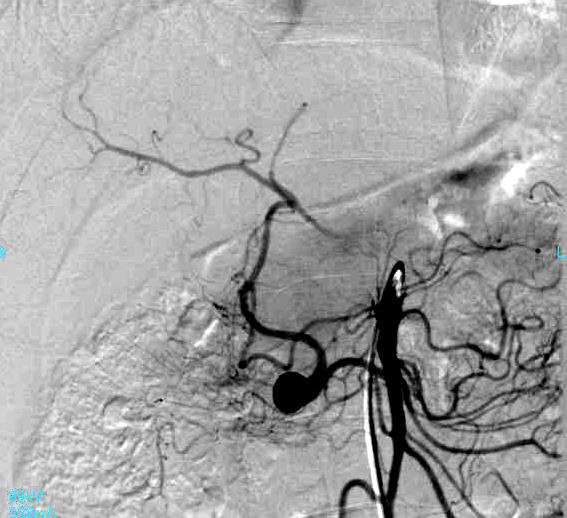

肠系膜上动脉造影显示肝动脉通过扩张的胰十二指肠动脉弓显影。2cm动脉瘤起自胰十二指肠下动脉。

治疗后肠系膜上动脉造影证实,弹簧栓子填塞瘤囊,动脉瘤近端和远端动脉也由弹簧栓子闭塞